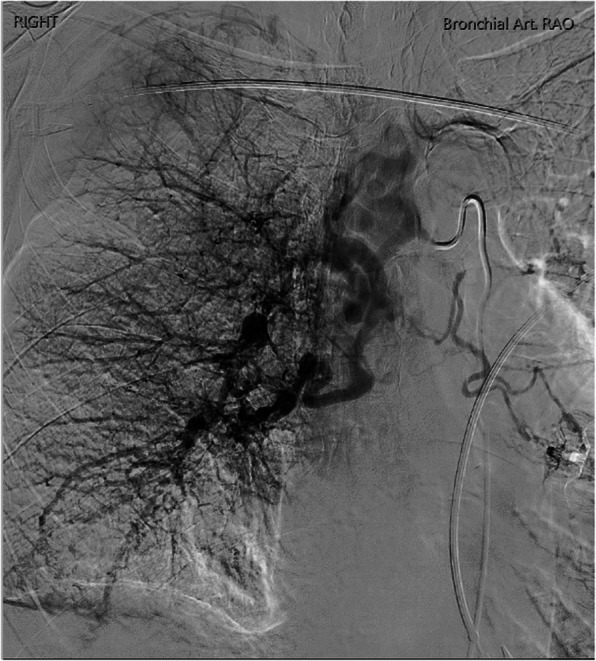

Fig. 3.

Delayed phase angiography demonstrated hypervascular parenchymal blush predominantly in the right upper to mid zones with drainage primarily via the right upper pulmonary vein